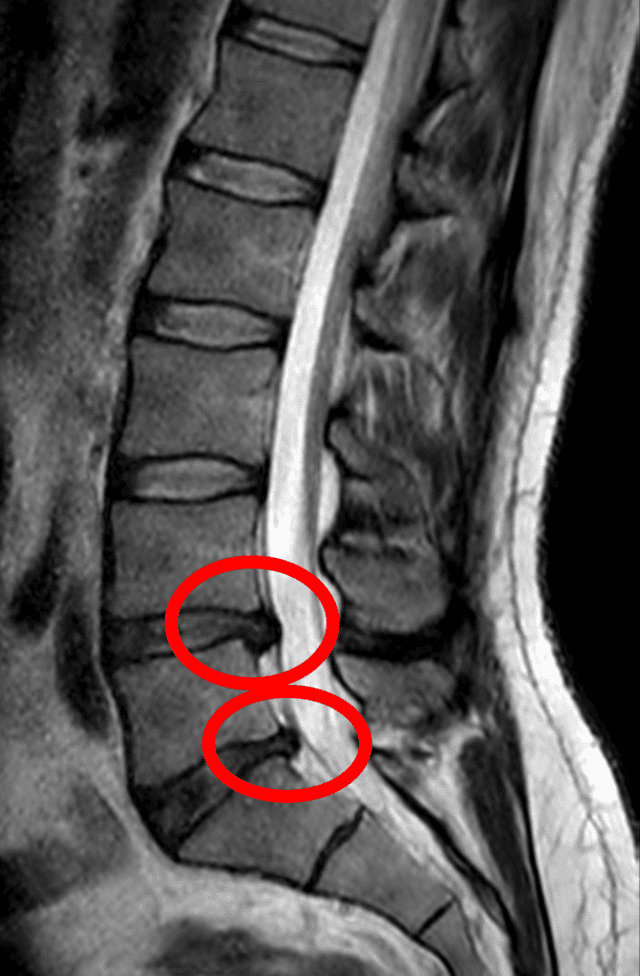

Think of the discs between your vertebrae as small, jelly-filled shock absorbers. They provide cushioning and allow for flexible movement of the spine. A herniated disc (also known as a slipped or ruptured disc) occurs when the soft, gel-like centre (the nucleus) pushes out through a tear in the tougher exterior wall (the annulus).

When the disc material herniates, it can press directly on the spinal cord or nearby nerve roots. This compression, along with the chemical irritation from the disc's inner material, is what causes the intense pain and neurological symptoms.